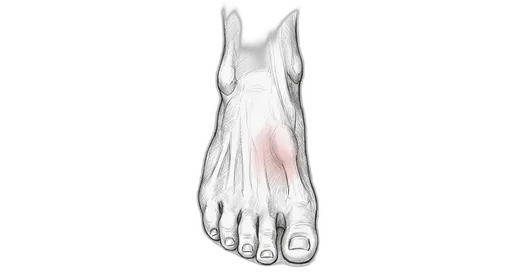

Foot & Ankle Exercise Guide

Choose your condition below to get started with exercises and stretches designed by Dr. Patish.

Pick your condition below, and you'll find your personalized exercise program — with medical illustrations, step-by-step instructions at three intensity levels, and clear guidance on when to call our office. Every protocol here is the same one Dr. Patish prescribes to patients in the clinic.

Forefoot & Toes